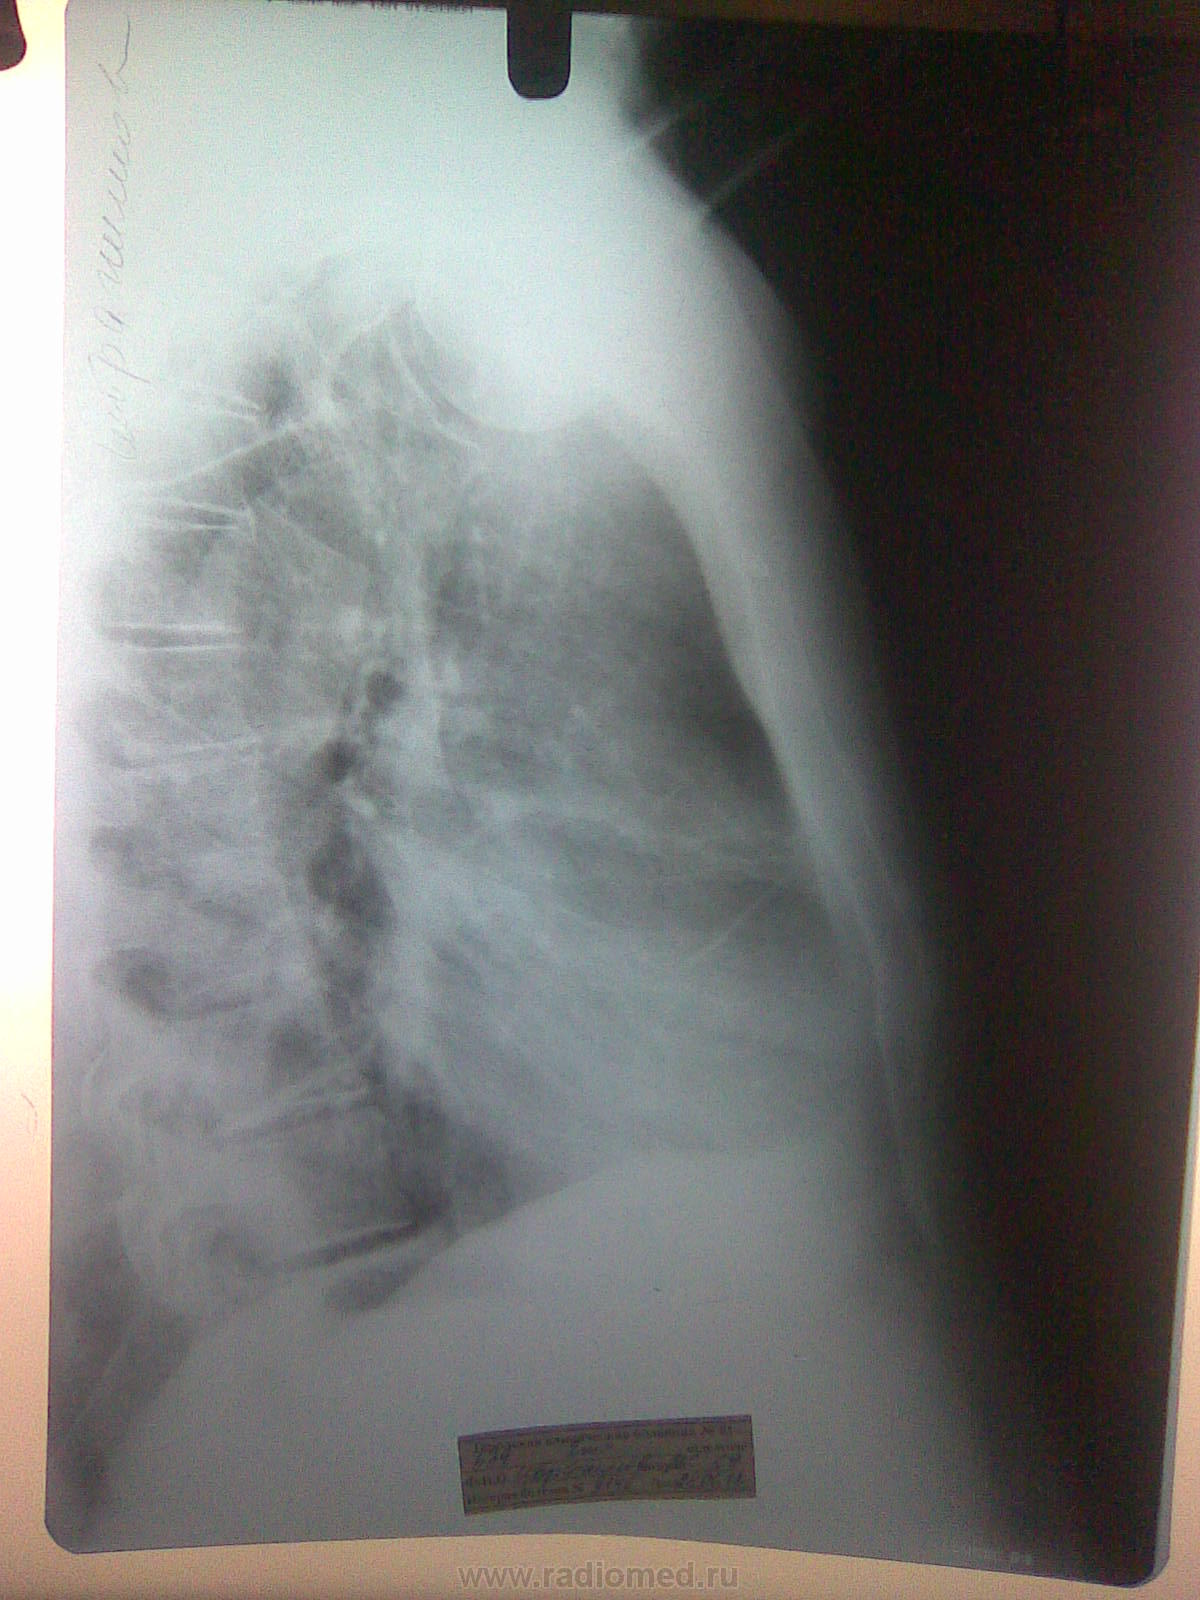

Это снимки от 28.06.12 года - прямой и правый боковой ( динамика )!

Снимков при поступлении у меня нет - есть описание: В легких умеренная перегрузка по МКК. Правый синус плохо просматривается ( жидкость ? ). Сердце умеренно расширено влево. Аорта плотная. Эти снимки в динамике, через 10 дней. А/б пациент не получал...

Снимки сделаны недопустимо «мягкими лучами», контраст чрезмерный и потому потеряно много информации в тенях и в светах. Всё, что упомянули коллеги, здесь может быть. Tbc, если и есть не может объяснить имеющуюся симптоматику. Скорей всего есть немного плеврального транссудата справа. Проверить на УЗИ – минутное дело.

Инфильтрация в в 9 и 10 справа с плевральной реакциией. А природа любая, но активный ТБС маловероятен. Если заказана КТ - нужно делать...

Изменения в верхушках есть, но не думаю, что ТБЦ. Для такого возраста характерно и в норме. Справа внизу похоже на инфильтрацию, но это возможна и ТЭЛА.